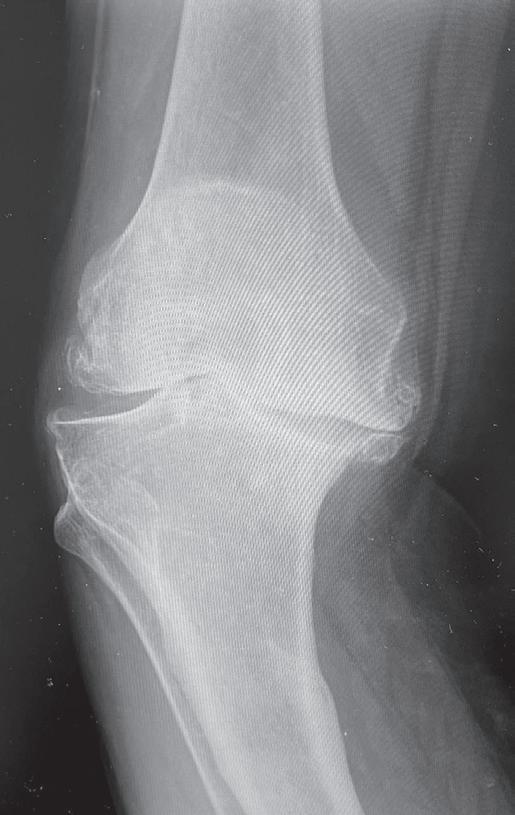

Obr. 19.3: Valgózní deformita kolenního kloubu (a) a rentgenový  nález úhlové deformity s nálezem pokročilých artrotických  změn (b)

(předozadní a bočná). Na rentgenovém snímku se gonartróza zpočátku projevuje přihrocením interkondylické eminence a subchondrální sklerózou v místě přetížení, později zúžením, případně až zánikem kloubní štěrbiny, vznikem osteofytů, pseudocyst a případnou úhlovou deformitou. Dle nálezu rovněž klasifikujeme stupeň gonartrózy podle Kellgrena-Lawrence (viz kap. 17, obr. 19.4), což má praktický význam v indikaci farmakoterapie i balneoterapie.